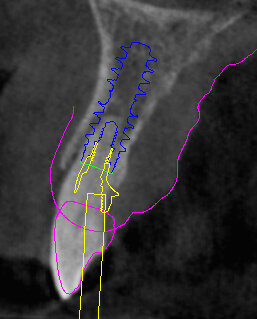

Il piano di trattamento prevede l’estrazione degli elementi dentali, l’inserimento di due impianti e la realizzazione di una protesi fissa di quattro elementi. Il problema da gestire è quello della fase provvisoria. Non è ipotizzabile una protesi mobile e quindi programmiamo di inserire subito dopo l’intervento un provvisorio immediato. Questo ci consente di condizionare da subito i tessuti periimplantari e anche le zone dei ponti. Si rileva un’impronta digitale (Figg. 5, 6), e la programmazione degli impianti viene effettuata con un software di chirurgia guidata (Fig. 7) e la posizione degli impianti nello spazio biologico e nello spazio protesico viene fatta sulla base di una ceratura diagnostica (Figg. 8, 9). Inseriamo gli impianti virtuali nell’osso disponibile (Figg. 10-13) e in relazione all’aspetto protesico correggiamo l’asse di inclinazione degli impianti con componenti secondarie angolate a 17° (Figg. 14, 15). Questo ci consentirà di realizzare una protesi avvitata con i fori situati nella zona palatale.

Fig. 11 - Posizionamento virtuale dell’impianto 2.2.

Fig. 13 - Cross impianto 2.2.